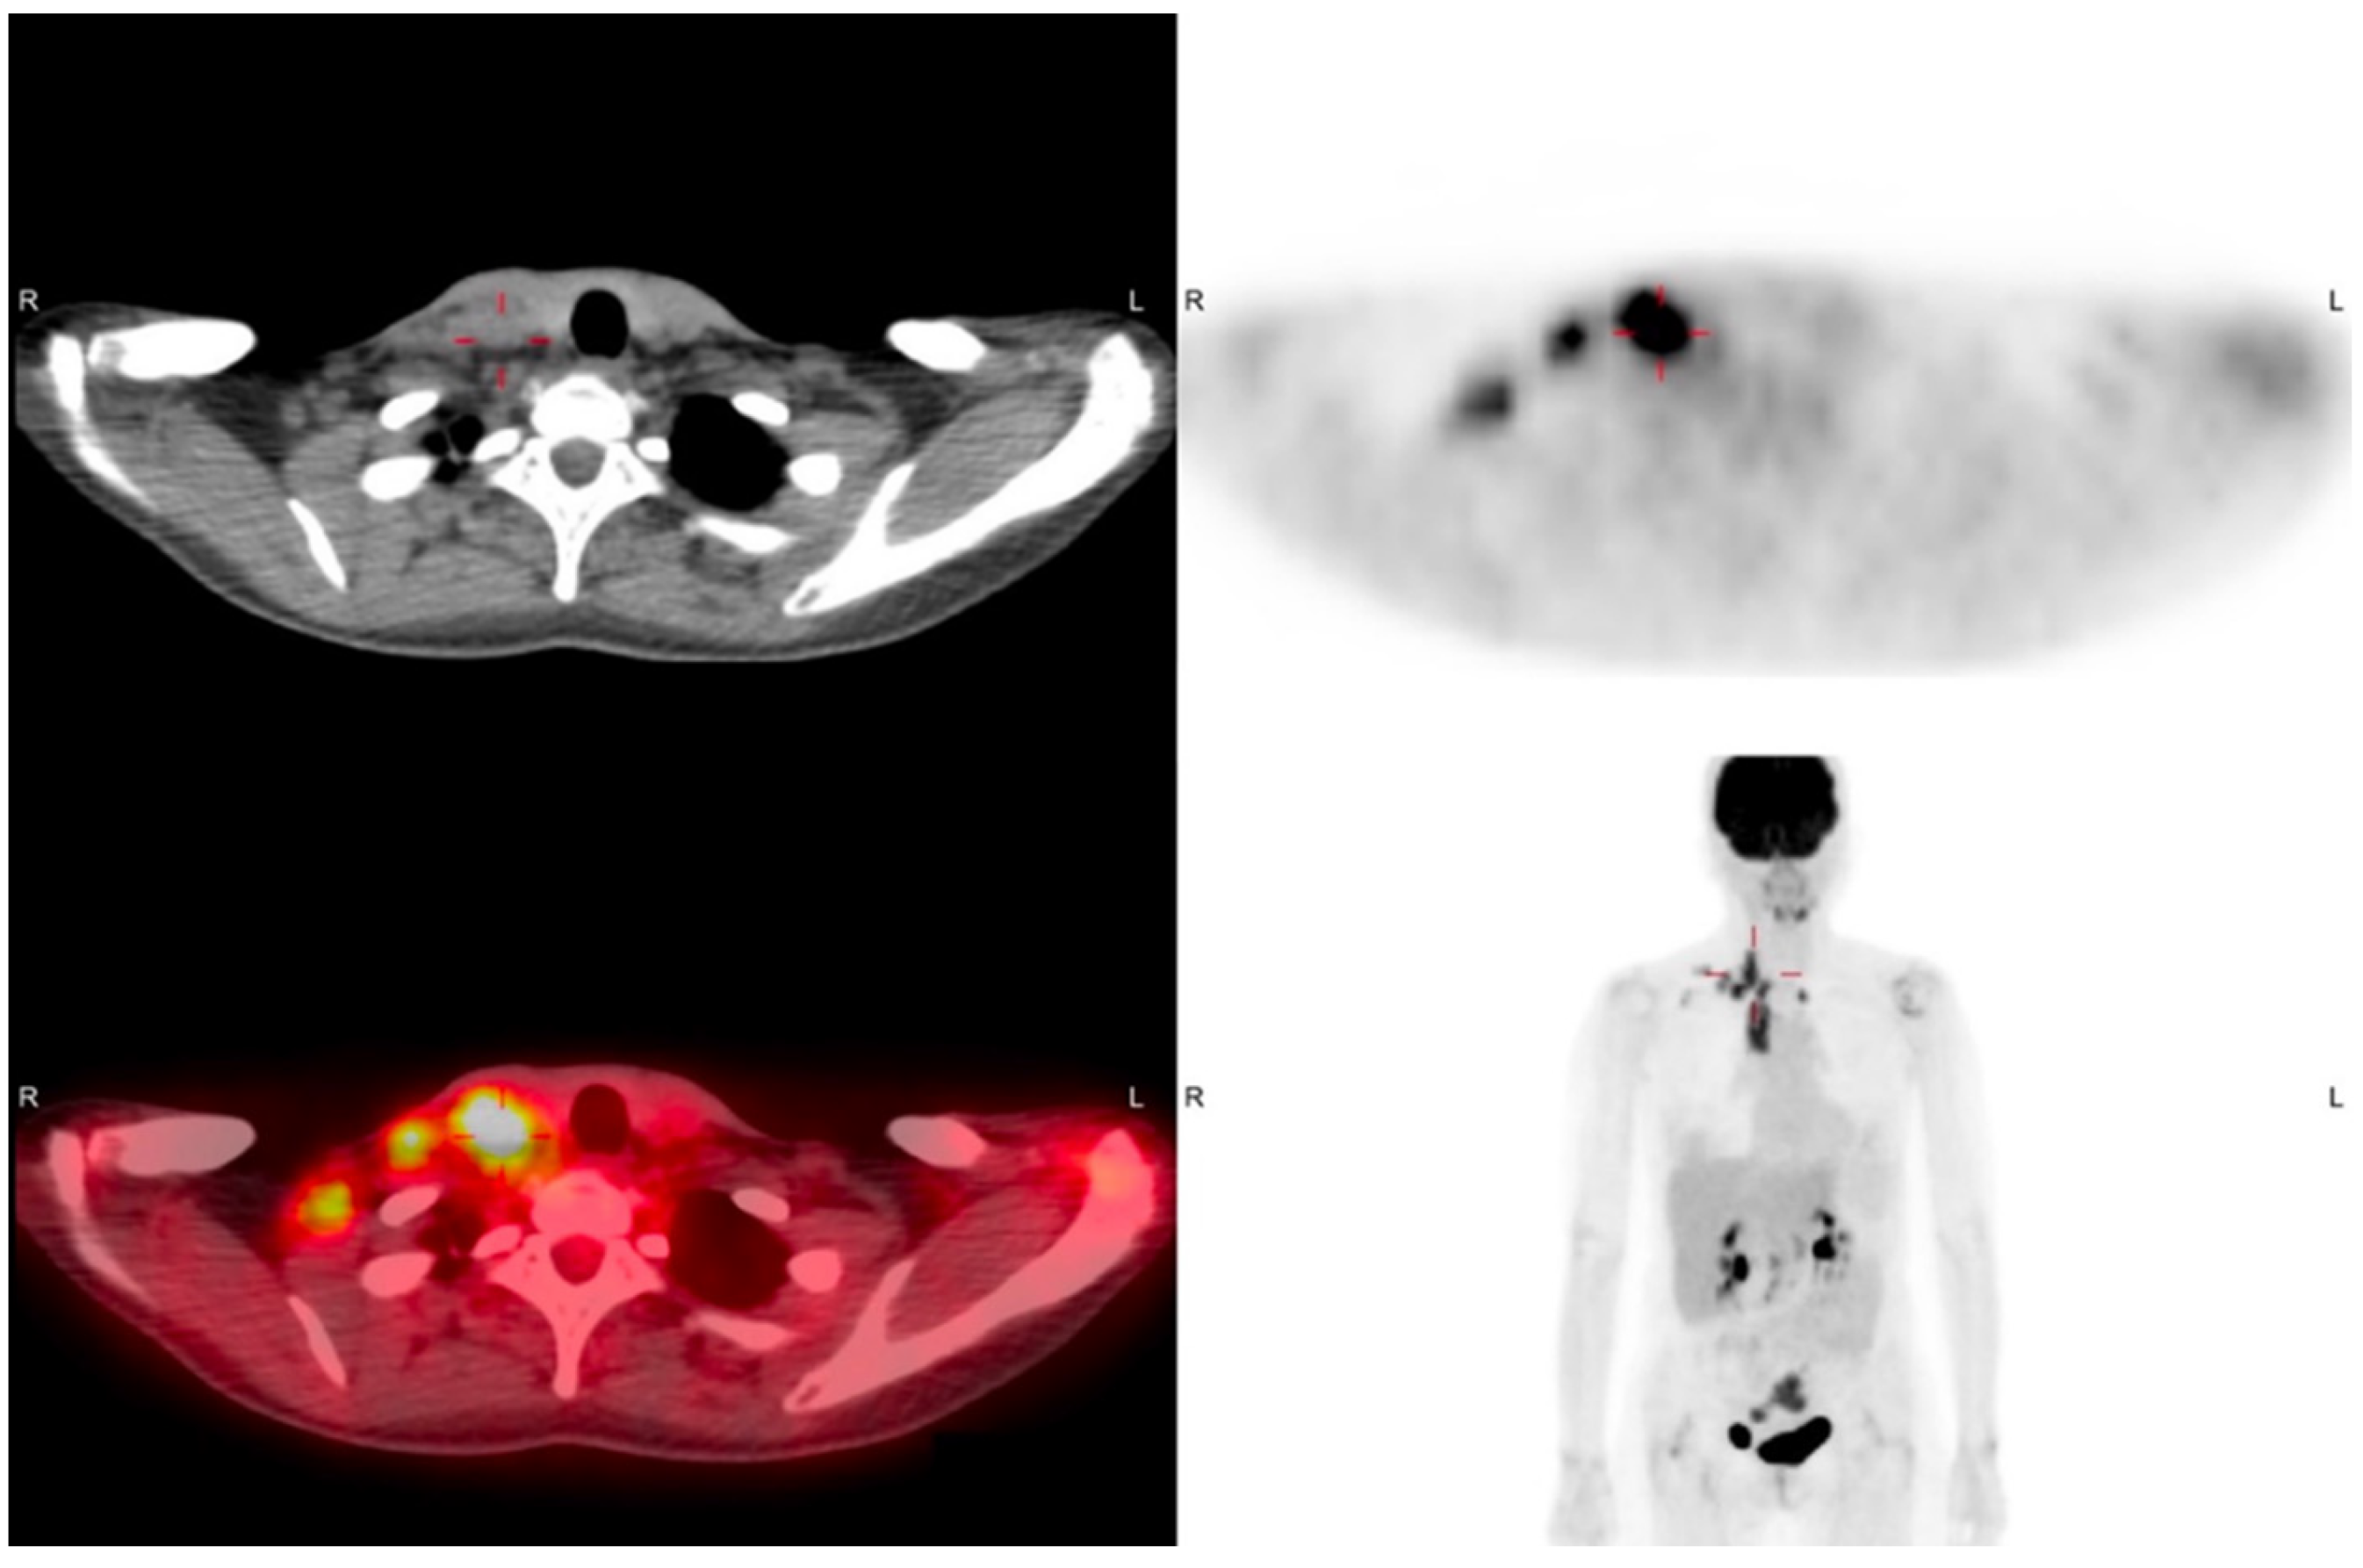

2. Case Report